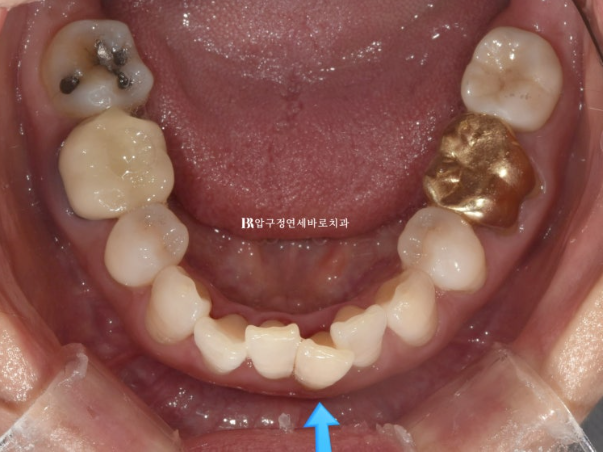

파란 화살표 부분은 잇몸이 주변치아에 비하여 내려가 있습니다.

그 이유는 배열에서 가장 벗어난 치아여서 입니다.

제자리로 넣어주면 잇몸이 회복되기도 합니다.

위 앞니 블랙트라이앵글은 치간삭제를 통해 줄었으나 삐뚤했던 아래 앞니가 가지런해지면서 블랙트라이앵글이 생겼습니다.

아래도 마찬가지로 치간삭제를 통해 블랙트라이앵글 사이즈를 줄였지만 치간삭제는 치아에 무리가지 않는 선에서 하는 것이 좋습니다.